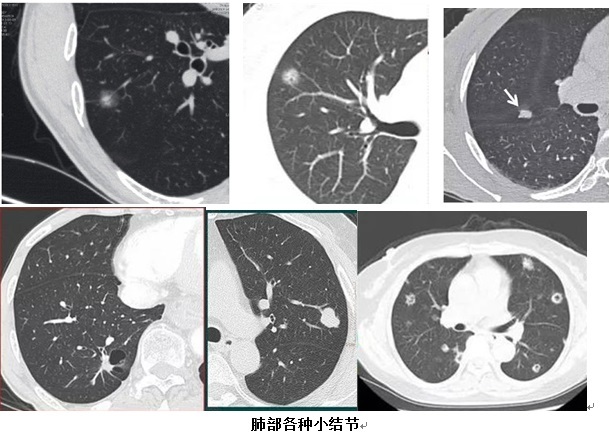

这个在体检单上“吓倒”不少人的肺部小结节,其实是通过肺部CT检查发现的,直径在10 mm左右的结节病变。肺部小结节多为体检时偶然发现,大多无典型症状,分布于肺内的各个部位,多为单个、亦有多发的情况。

中山大学附属第三医院放射治疗科主任徐向英教授提醒,肺部小结节并不等于早期肺癌。肺内多种疾病都会形成结节,比如良性的如炎症、结核、霉菌、亚段肺不张、出血、淋巴结及寄生虫等;恶性的则可能是原发性肺癌或其他肿瘤导致的肺内转移癌。

4、检出的肺结节大小在10 mm左右,影像学上是否伴有血管穿行、伴有毛刺样、空泡征、分叶状或毛玻璃样改变,胸膜是否伴有凹陷或牵拉征象,或者定期检查结节不断增大等。